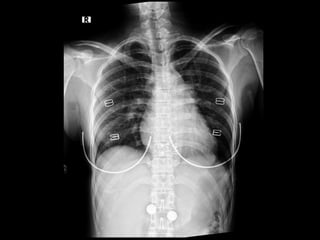

CXR

Management at ER •Check neurovascular + Immobilization (on arm sling) • Imaging CXR Film right arm AP, transcapular Y view Film skull AP, lateral, towne, water • Medication Pain control tramol 50 mg IV stat then q 6 hr plasil 10 mg IV prn q 6 hr ATB cefazolin 1 g IC stat then q 6 hr Vaccine Tetanus vaccine 0.5 ml IM